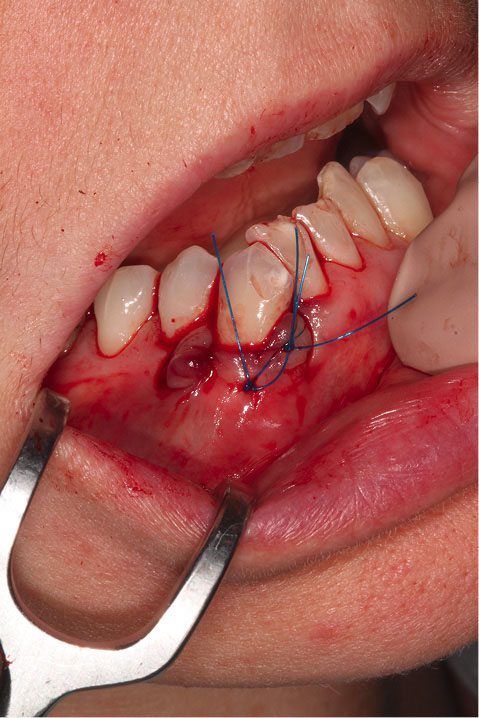

Figure 2 shows the final tunnel preparation before the placement of CTG. Figure 3 shows the harvested CTG positioned on the exposed root surface to check its dimensions before placement inside the tunnel on the buccal aspect of tooth #43. Figure 4 shows suturing after the CTG has been positioned inside the tunnel. Please note that the sutures were kept longer than usual to prevent the poking of the suture ends into the lower lip and buccal mucosa. Figure 5 shows the postoperative condition at five-week interval.

japid-12-90-g004

Figure 4. Suturing after the CTG has been positioned inside the tunnel. Please note the sutures were kept longer to prevent poking of the suture ends into the lower lip and buccal mucosa.